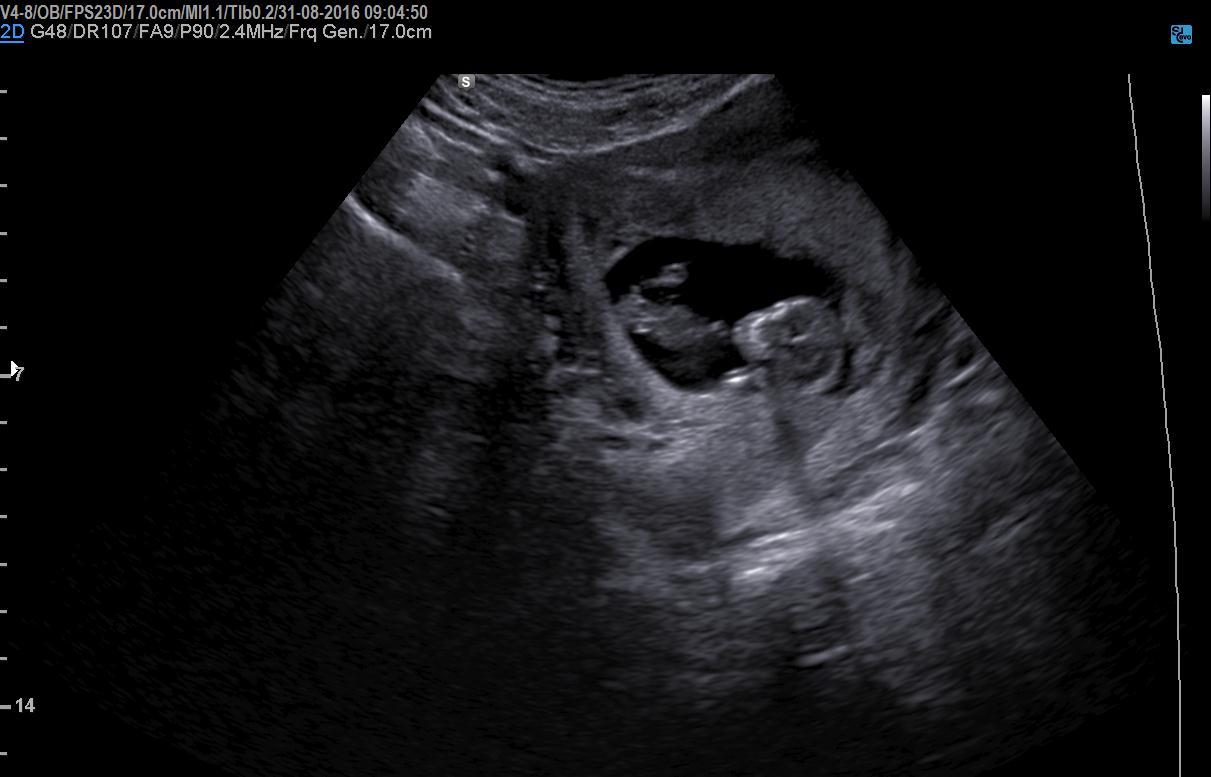

Girl or boy nub??? HELP pls any guesses

Hi guys. Boy or girl nub??

Attachment 33221